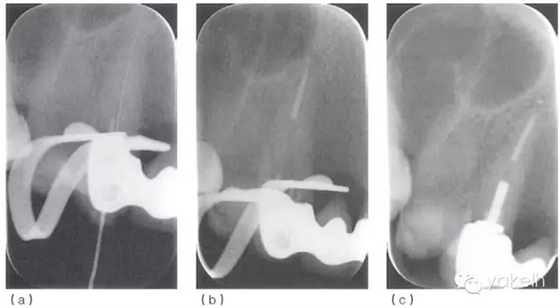

¤¤口外檢查可見右頰中度腫脹,右側鼻唇溝消失。口內檢查可見牙列中有部分修復體。13腭側可見窩洞暫封,唇側近頸部黏膜可見一處潰瘍,10mm×15mm(圖 5.2.1a),其他軟組織正常。13對EPT和溫度測試無反應,叩痛,根尖X線片(圖 5.2.1b)顯示根尖周透射影。

圖 5.2.1(a)次氯酸鈉意外進入根尖周組織24小時之內,引起潰瘍。(b)13術前X線片。

¤¤使用根尖定位儀確定根管的工作長度,拍攝X線片(圖 5.2.2a)加以驗證。采用化學-機械方法進行完善的根管預備后,使用牙膠和根管封閉劑,采用熱垂直加壓技術進行根管充填(圖5.2.2b,c)。1個月后復診,患者無癥狀,潰瘍變小,僅黏膜表面遺留瘢痕(圖 5.2.3)。

圖 5.2.2(a)13確定工作長度的X線片。(b)13根管充填中X線片。(c)13根管充填后X線片。